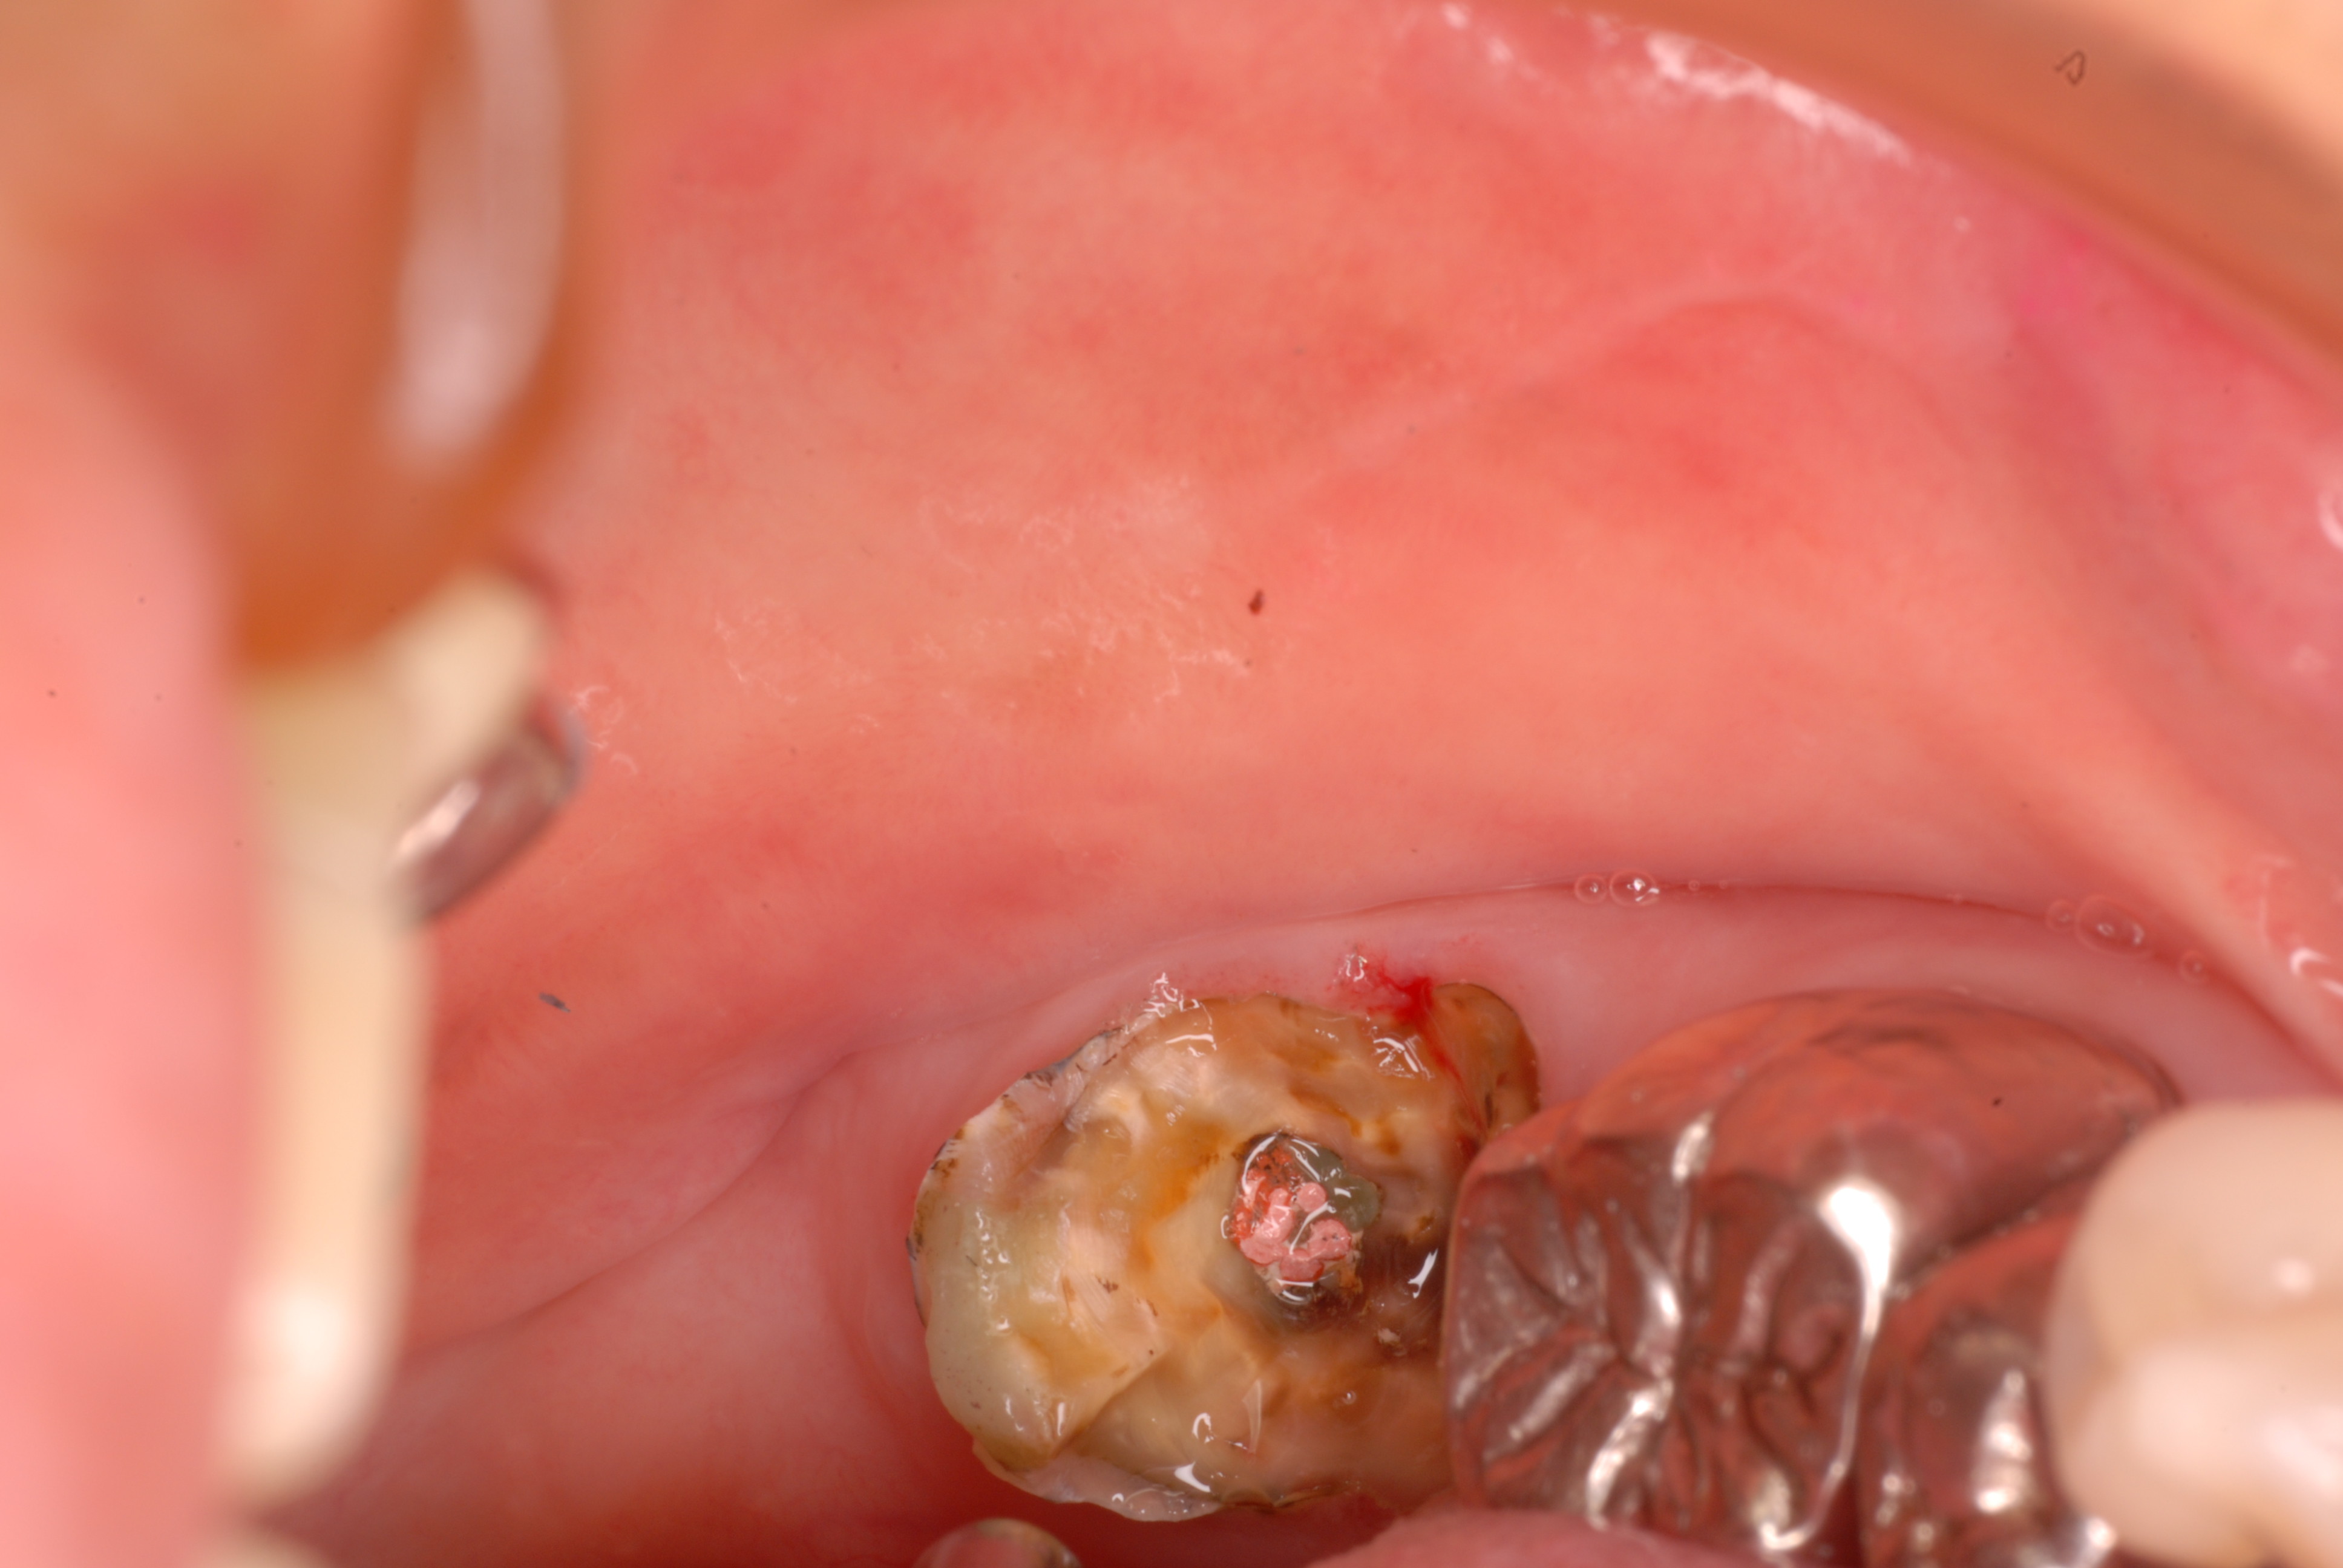

以前来られて痛みがなくなると或いは費用?の話しになると来なくなり仮の歯が壊れると又来るという方がいました。

根管治療という歯の中の治療は、保険で完全にやろうとするとかなり赤字になる部門なんです。

だから被せ物とかで費用を請求しないと採算に合いません。だからか解りませんが、治療の失敗が多いのです。

左下の一番奥の歯の治療がいい加減なようです。

そして歯周病を併発していて別の歯科医院で抜くしかないと言われて何とかならないかと当院に来られました。

前の歯科医院では抜歯した後インプラントを薦められたそうです。

確かに保険で治療して成功しても毎回数千円にも満たない治療費となり経営を考えると憂鬱の一言です。

だから一度インプラントを導入した歯科医院では、安い保険の治療を諦める傾向にあるのではないかと想像していました。

現実にそういう事を目にして安易に人工の金属歯根であるインプラントの導入は危険な感じがします。

左下の一番奥の歯の治療がいい加減なようです。しかし治療をしてみると滅菌しながら治療をすることの困難さを痛感しました。

保険では安すぎます。(ため息)

三本ある根管の内、難しい手前の根幹の治療が為されていません。顎の骨に黒い影ができています。

根管治療終了です。

骨の部分は健康を回復しています。影がありません。治療が成功しています。

費用を安く済ませる為に仮歯だけで時間を取るという事は許されません。

これからは仮の歯でも2万円ぐらいいただかないといけないかと思う事もあります。それだけ時間と手間がかかるのです。

反対側の大臼歯には分岐部に深い虫歯と深い分岐部病変がありますが、虫歯の治療後は歯周病が酷いのに来られなくなりました。

上のレントゲンでも歯根の間に影があります。悪性の分岐部病変ですね。